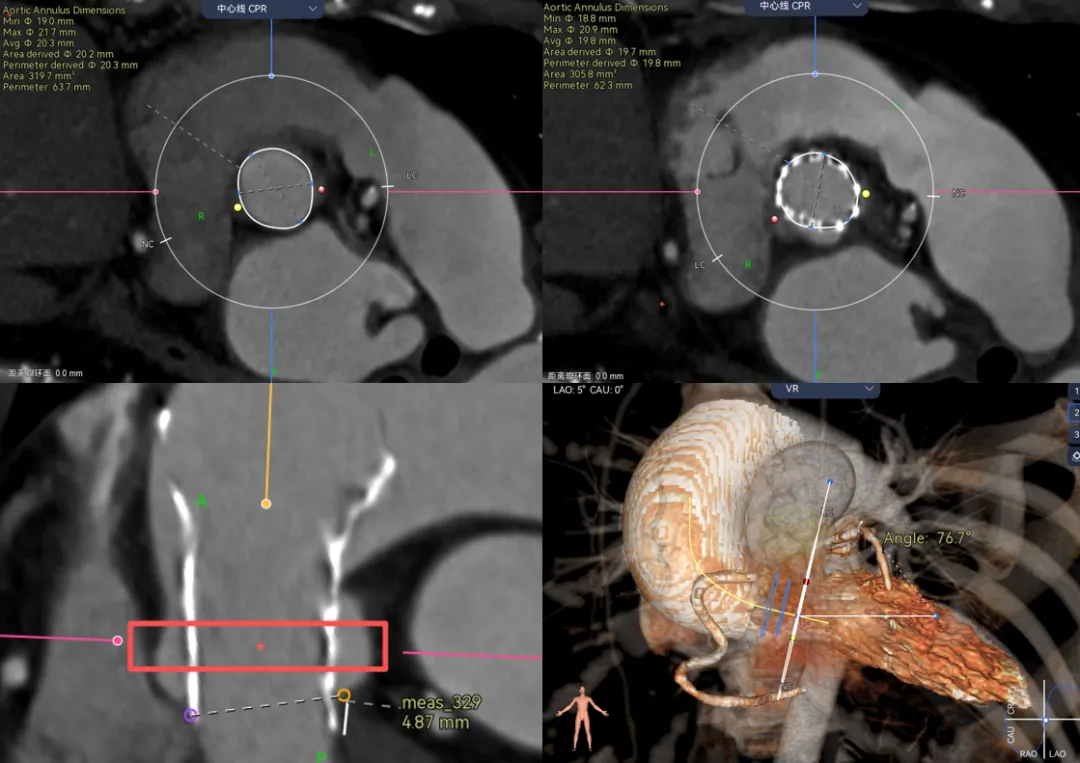

瓣上测量是CT评估中比较重要的一环,也是很吃经验的一个环节,圈画在哪里,画大画小,如何预判瓣膜植入之后大概的锚定区域和封堵区域。以及STJ和冠脉的遮挡可能性,每个技术支持画起来千差万别。

看位置:我们在测量的时候需要评估钙化和升主对瓣膜的推挤作用,来预测瓣膜在每个地方大概位置在哪里。

病例1 - 钙化集中在大弯侧,将瓣膜像小弯侧推挤,单边钙化要注意识别冠脉风险,并不是二叶瓣就没有冠脉风险了。可以看到图中的瓣膜距离冠脉开口很近。